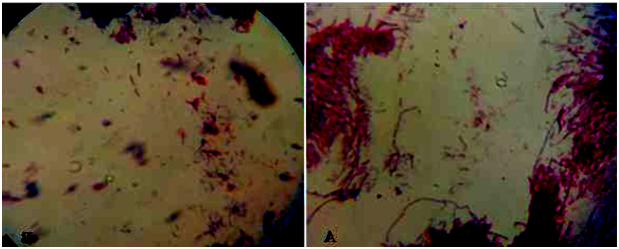

Mycobacterial culturing was conducted from characteristic tubercle lesions of which 7.5% (3/40) showed growth on primary culture media. Of those cultures which showed visible colony, 5% (2/40) were seen on Lowenstain-Jenson (L-J) media enriched with glycerol and the rest 2.5% (1/40) were grown on L-J media enriched with pyruvate. Three grown cultures were subjected to Zeihl-Neelsen staining technique in order to check the presence of acid fast bacilli. 5% (2/40) of the cultures were found to be acid fast positive. The observed colonial morphology was smooth whitish or yellowish color, sticky, off-white and breaks apart easily (Figure 7). The results attained of Z-N staining were cocci, short and some long rod shaped and also found in single and clumps (Figure 8), (Table 6).

Figure 8 AFB staining positive isolates from mycobacteriological culture colony grows. From lymph nodes (Mesentric and retropharyneal) TB lesion (arrows indicate acid fast bacilli which a short and long, in Single or clump).